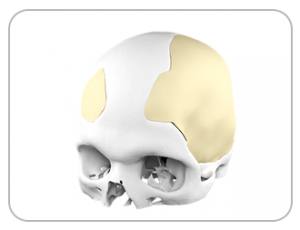

Shankar was rushed to hospital in an unconscious state and was diagnosed with stroke and consequently paralysis in his right hand. After decompressive craniotomy, he suffered from subsequent CSF accumulation and infection as a consequence of which, his bone flap had to be replaced. Medicad Implants developed an anatomically precise cranial flap replacement for Satish with 3D printed Titanium. Post the implant placement Satish has recovered well and regaining control of his motor functions.

DEFECT

TITANIUM IMPLANT